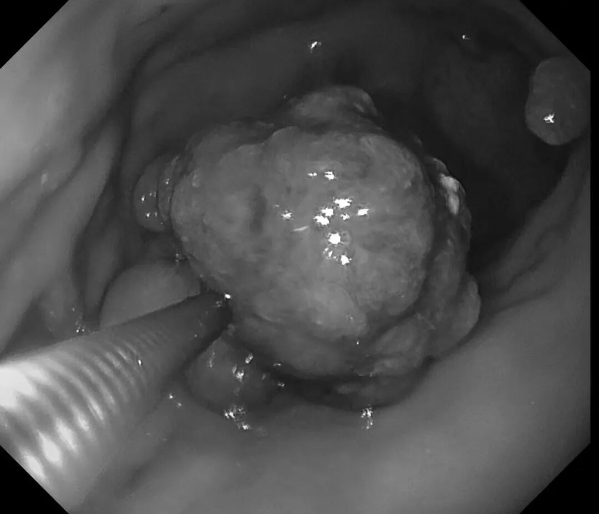

患者王阿姨(化名),65岁。平日里胃肠偶有轻微不适——腹胀,女儿考虑到母亲的年龄,想做个胃早癌筛查,遂带王阿姨来新镜界做胃肠镜精查。

检查中:胃体发现重要异常——胃体巨大息肉,直径约40x40mm!表面充血,带有亚蒂,未来有可能发展为胃癌,健康隐患极大!经与患者家属沟通同意,綦盛麟教授采用ESD(内镜下黏膜剥离术)成功切除巨大息肉。